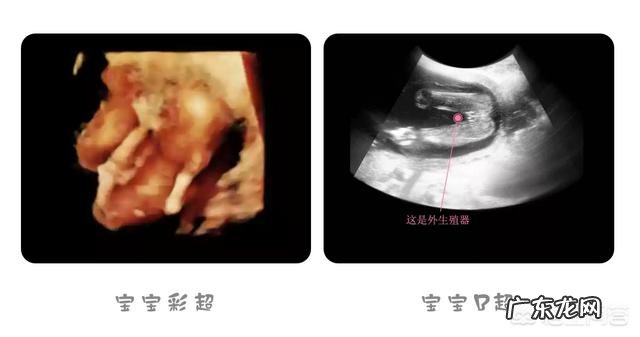

(孕4个月胎宝宝头臀长大约109mm,体重约86g)